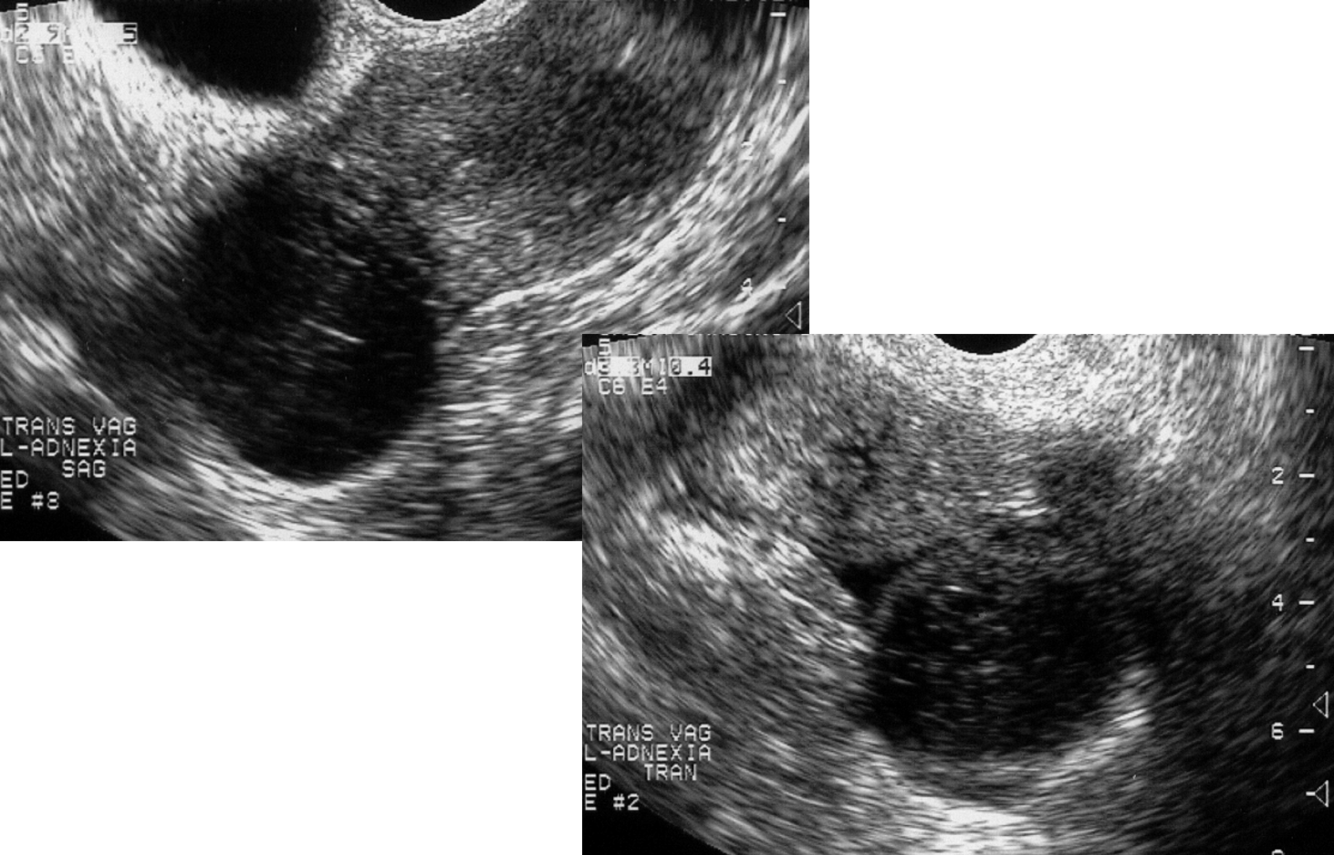

Follicles

Polycystic Ovarian Syndrome“string of pearls”

ovarian volume > 10 cm3

peritoneal inclusion cysts